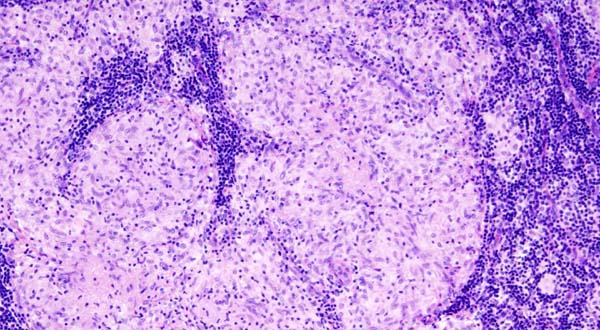

Por primera vez en España , mañana se celebrará el Día de la Concienciación de la Sarcoidosis, una enfermedad que no tiene cura, caracterizada por una inflamación anómala de los tejidos de un órgano debido a un fallo en el sistema inmunologico que afecta a su normal funcionamiento.

Esta enfermedad afecta a unos órganos más que a otros, principalmente pulmones, ganglios linfáticos, piel, corazón, nervios, cerebro, ojos e hígado, pudiendo atacar a más de uno a la vez. Llegar al diagnostico es difícil tarea para el facultativo, porque los síntomas suelen confundirse con otras patologías, como por ejemplo la tuberculosis en casos de pulmón, o la fibromialgia en los casos de la neurosarcoidosis.

Se desconoce, si bien se sospecha, que puede tener origen genético y que un fallo en el sistema inmunológico la desarrolla. No es contagiosa y no tiene cura y en algunos casos la remisión de la enfermedad es espontánea y no necesita medicación alguna.